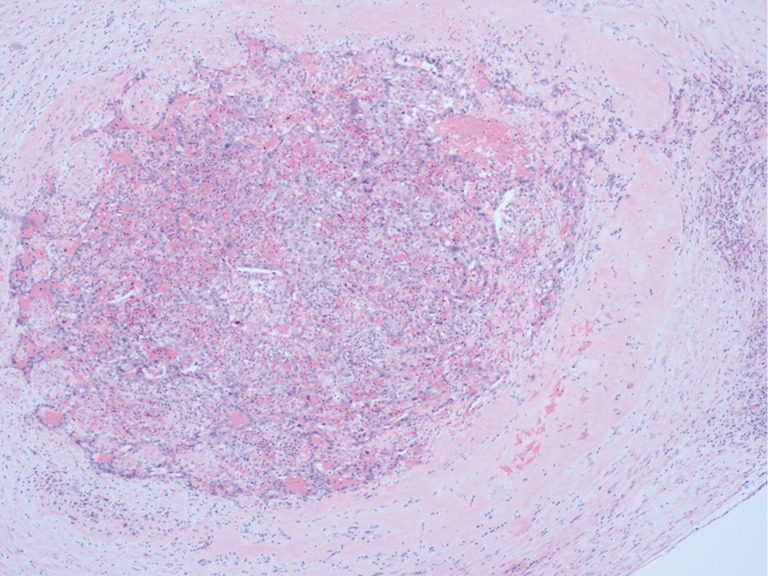

Case description: We presented a case of PHC with specific clinical examinations and treatments. The patient reported that he suffered from a history of chronic viral hepatitis B, laboratory tests showed elevated serum alpha-fetoprotein (AFP) levels. No significant liver mass was found on imaging, the contrast-enhanced abdominal computed tomography revealed a slightly nodular low-density shadow in the head of the pancreas. The patient received neoadjuvant chemotherapy combined with programmed cell death protein 1 (PD-1) antibody and he underwent radical resection of pancreatic cancer. The post-operative histopathological examination of the resection specimen revealed a diagnosis of poorly differentiated PHC. Half a month after the surgery, this patient's serum AFP dropped to within the normal range. The patient recovered without complications, and regular reexaminations showed no signs of tumor recurrence and metastasis.